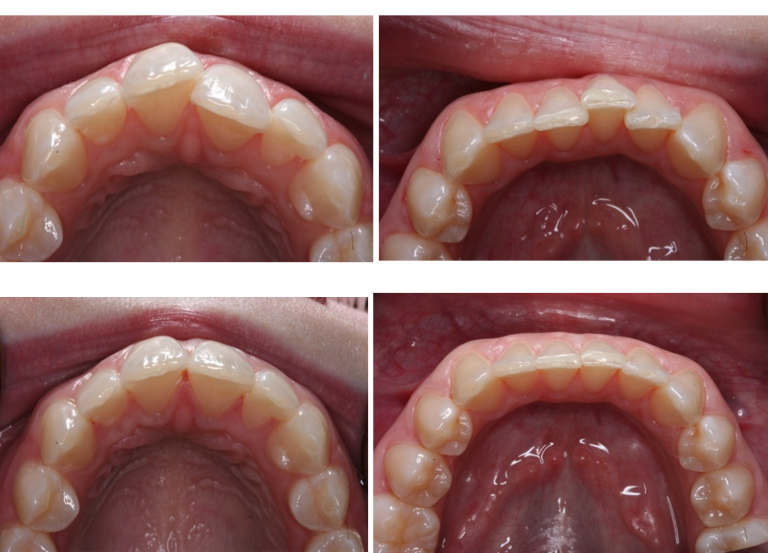

Invisalign — North Hollywood, CA

This North Hollywood patient came in with crowded upper and lower teeth and a noticeable crossbite affecting both appearance and bite function. After 14 months of Invisalign clear aligner treatment with Dr. Elzayat at A-Dental Center, the result is a straight, even smile — achieved without a single metal bracket or wire.